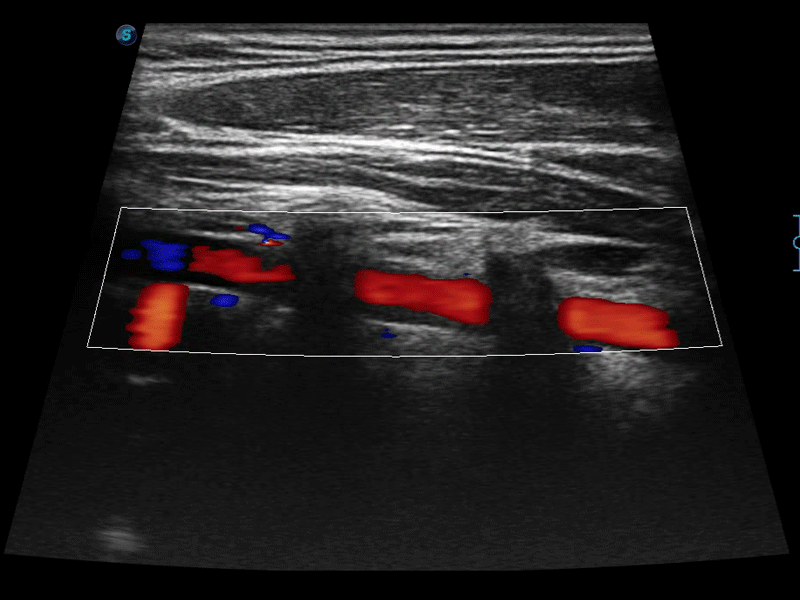

高分辨率血流成像技术提高了对低速血流信号的检测能力。在提高空间分辨率的同时,也克服了血流外溢现象,为用户提供更加真实的血流动力学信息。

通过色彩血流和实时宽景相结合,可观察到完整的静脉或动脉的血流,方便医生检查。实时扫查过程中,如有任何操作失误也可以很容易地进行回扫擦除,而不会中断扫查。

自动识别前后壁内膜厚度,为心血管疾病早期评估提供快速准确依据。